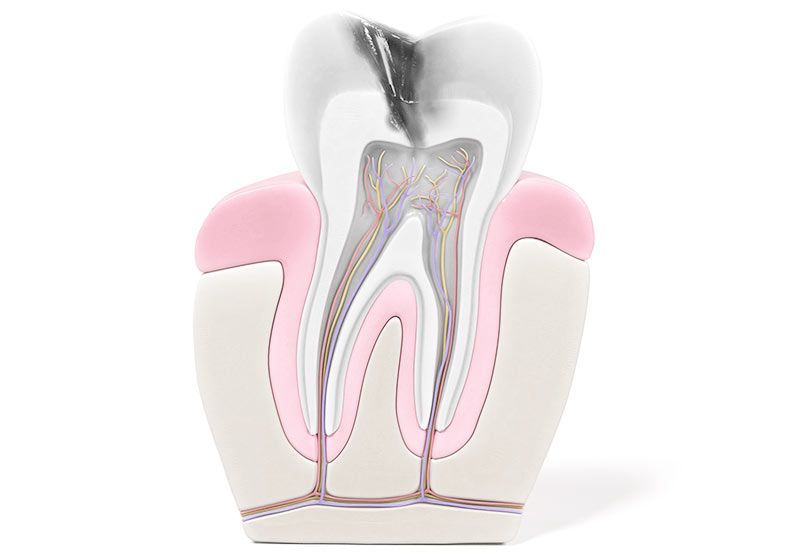

Die Endodontie befasst sich mit der Behandlung des Zahnmarkes, welches sich im Inneren des Zahnes befindet, auch als „Nerv“ des Zahnes bekannt.

Wenn sich das Zahnmark entzündet – z. B. durch eine tief in den Zahn reichende Karies – ist der Zahn gefährdet. Um ihn weiterhin erhalten zu können, wird meist eine Wurzelkanalbehandlung durchgeführt. In manchen Fällen kann es darüber hinaus nötig sein, ein kleines Stück der Wurzelspitze zu entfernen, um den Zahn vor dem Ziehen zu bewahren.